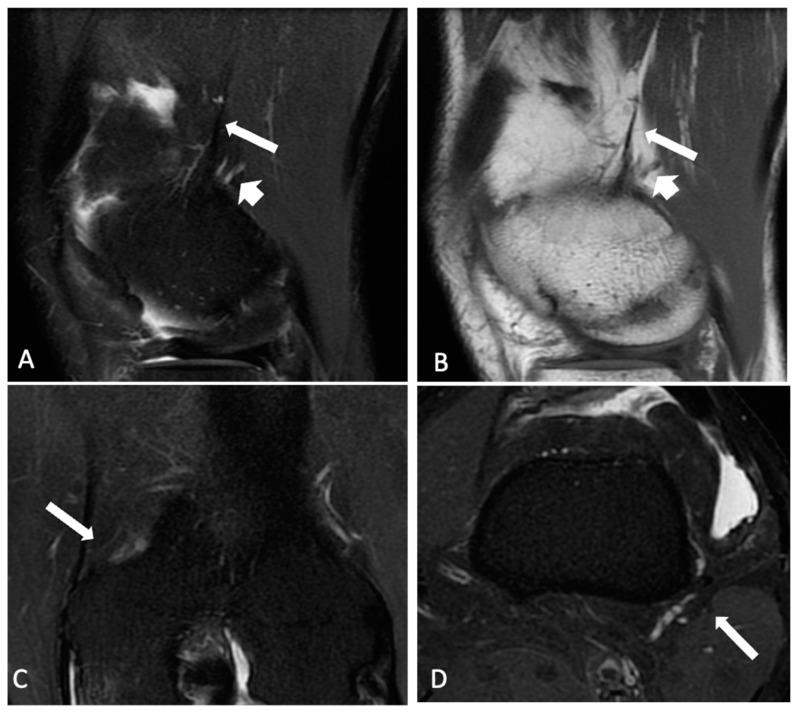

The association of ALL and KF injuries in anterior cruciate ligament (ACL)-deficient knees remain topics of conflicting research despite improved magnetic resonance imaging (MRI). We aimed to evaluate the rate of the anterolateral ligament (ALL) and Kaplan fibers (KF) injuries in adults with acute ACL injuries using MRI.

We retrospectively reviewed 64 patients with clinical and MRI diagnoses of acute ACL tears. Two radiologists analyzed and categorized the status of the ALL and KF in all patients as intact, partially injured, or completely injured. Interobserver agreement was assessed. Injuries to the collateral ligaments, ITB and posterior cruciate ligament (PCL) were also evaluated.

The mean age of the patients was 33 years. ALL injuries were observed in 46 (71%) patients, among whom 33 (71%) had partial and 13 (28%) had complete injuries. KF injuries were identified in 32 (50%) patients, with 28 (87.5%) of them having partial and 4 (12.5%) having complete injuries. Combined injuries of both ALL and KF were found in 25 (32.4%) patients (-value of 0.266). The agreement between the examiners ranged from moderate to substantial (Kappa between 0.55 and 0.75), with the highest agreement observed in cases of KF injuries (Kappa = 0.75).

ALL and KF injuries were prevalent in acute ACL-injured knees with rates of injury of 71% and 50%, respectively. ALL injuries were more frequent and more frequently severe compared to KF injuries.